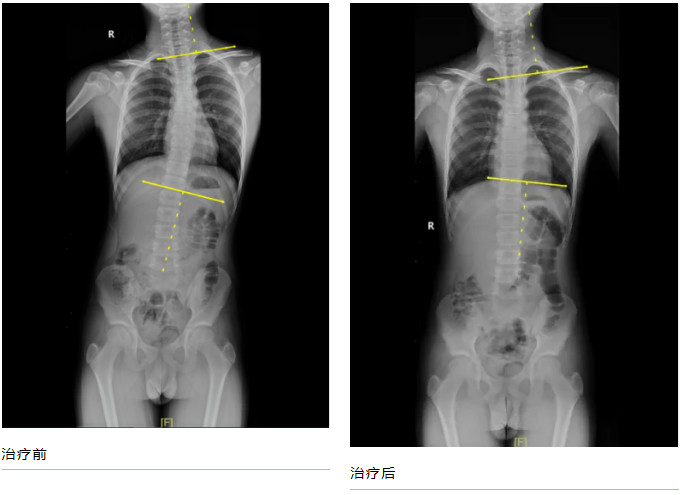

青少年小黃(化名),11歲,家屬發(fā)現(xiàn)脊柱異常1年余。查體:雙下肢真性長度等長,前屈試驗陽性,ATR≥5°。全脊柱正側(cè)位片示:“胸椎右側(cè)彎畸形,Cobb角= 23.44 °”。

經(jīng)過每周3次,共8周的規(guī)范治療后,小黃的脊柱側(cè)彎得到明顯矯正,復查全脊柱正側(cè)位片示:“胸椎右側(cè)彎畸形,Cobb角= 13.45 °”